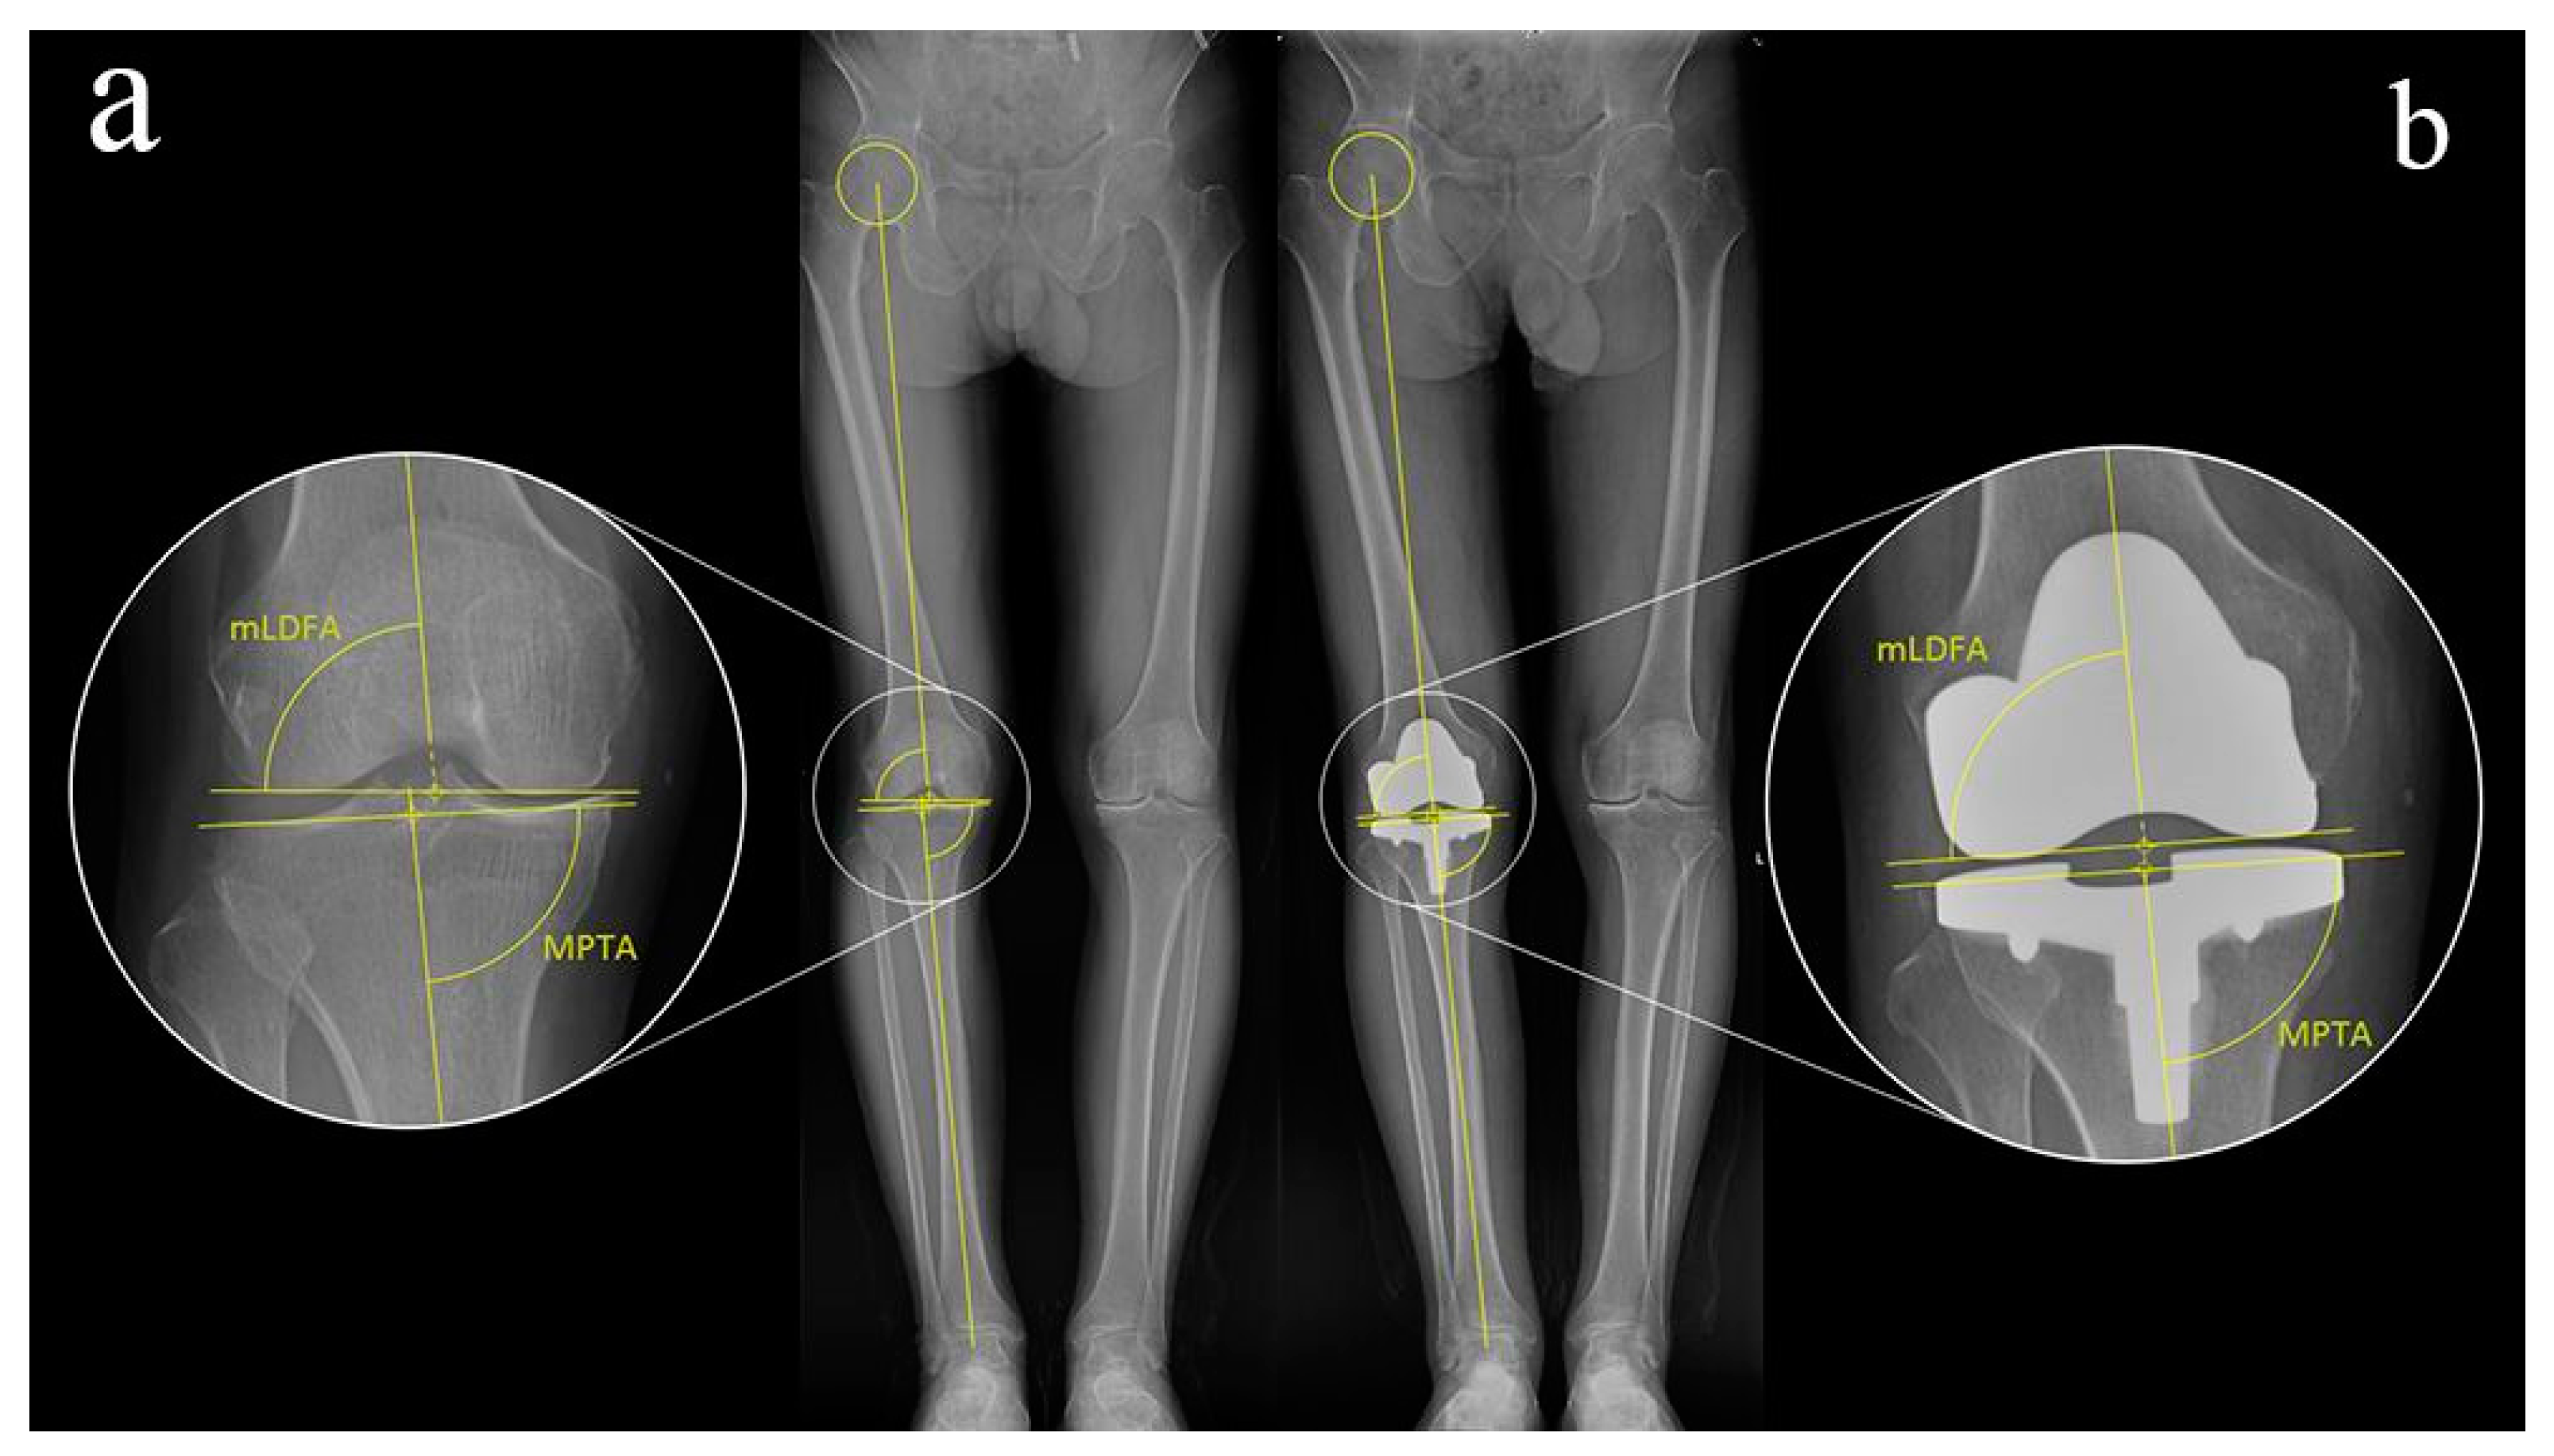

2.5. Assessment of the Accuracy of PSI

| PSI Group | Side of Joint Line (deg.) | ANOVA (p Value) | |||

|---|---|---|---|---|---|

| mLDFA | MPTA | PSI | Side | PSI * Parameters | |

| Engineer group | 1.40 ± 1.18 | 1.78 ± 1.44 | 0.010 | 0.466 | 0.576 |

| Surgeon group | 0.77 ± 0.66 | 0.82 ± 0.71 | |||